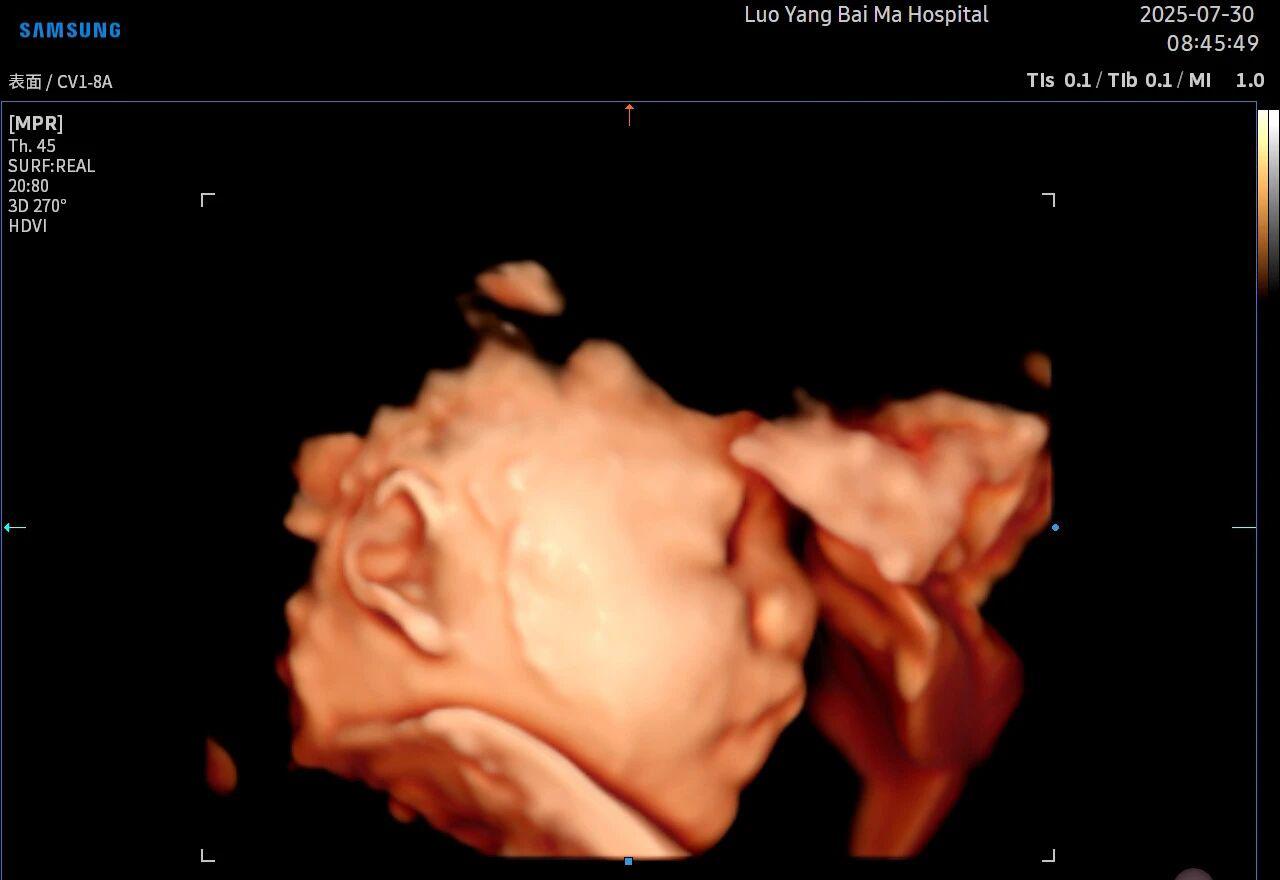

5D智能彩超拥有更高的分辨率和更强的图像处理能力,能够呈现出接近“IMAX电影画质”的细腻影像 。它采用一种被称为“水晶成像”的技术,能够穿透组织,将胎儿的骨骼、器官和组织结构以极其清晰、立体的形态展示出来。这种高清晰度对于观察胎儿微小的解剖结构细节至关重要,例如手指、脚趾、耳廓形态等,有助于医生发现一些在传统超声下不易察觉的细微异常,为排畸诊断提供了更丰富的视觉信息。

4. 温情互动,一次充满感动的“亲子会面”

除了严谨的医学诊断价值,5D彩超也为准爸妈们带来了无与伦比的情感体验。通过高清逼真的动态影像,您可以清晰地看到宝宝的每一个细微表情和动作,仿佛他(她)就在眼前。这份提前到来的“亲密接触”,不仅能极大地缓解孕期的焦虑,更能加深家庭成员与未出世宝宝之间的情感连接,让等待的每一天都充满更具体的幸福感。